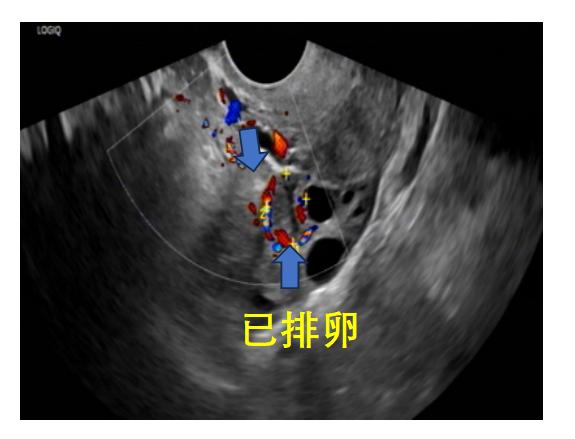

成熟卵泡消失或原成熟卵泡直径明显缩小,形态不规则,壁皱缩,卵泡内透声差,可见细弱光点,部分女性会出现子宫直肠凹积液,子宫内膜逐渐由A型转变为C型。